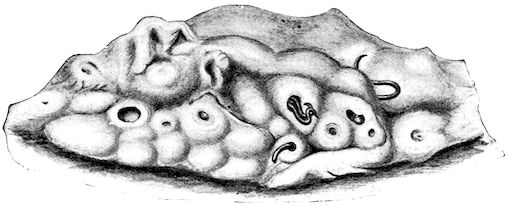

Fig. 8.—Transverse section through the middle region of the face in a pig suffering from osseous cachexia.

18In the final stages, the bones may be cut with a knife, and a time arrives when bony tissue seems completely to have disappeared; thus, as shown in Fig. 8 herewith, it was possible to cut the entire head of a pig into thin slices without the slightest difficulty. All parts of the head had been affected by the softening change.